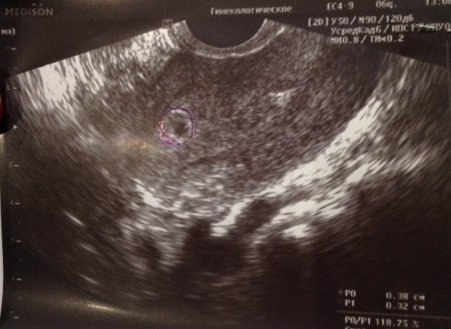

Прошло 4 дня и сегодня я пошла к врачу. Меня иногда беспокоят тянущие боли (как при месячных, только слабее).

Врач сказала, что все отлично!